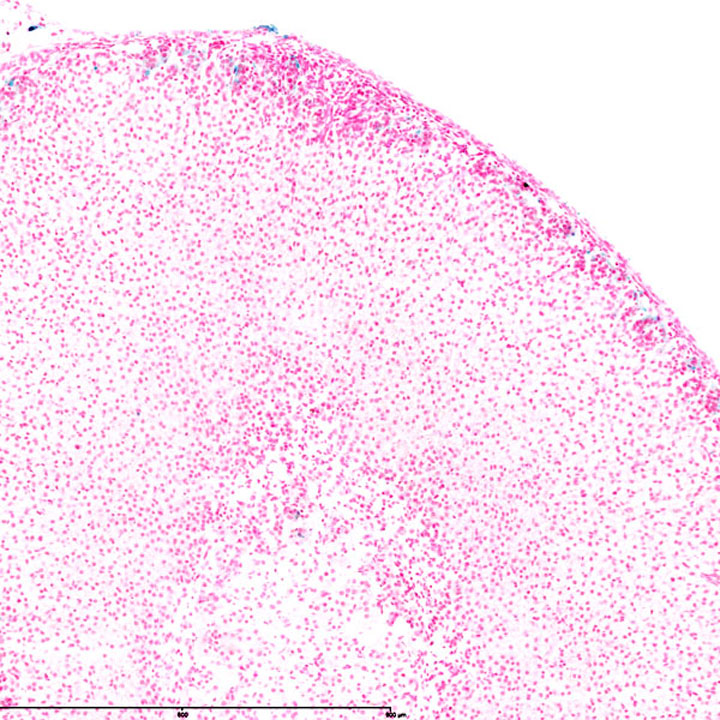

Fig. Acta1 Adrenal P56

J:193672

Fig. Acta1 Adrenal P7

Fig. Acta1 Pancreas P56

Full Image

Fig. Acta1 Pancreas P7